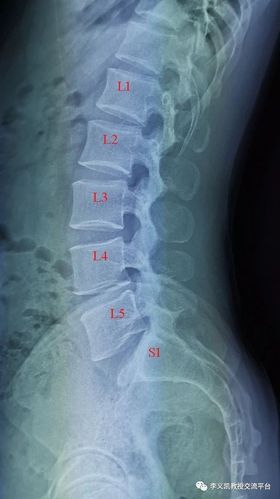

左侧骶骨翼骨折图片

左侧骶骨翼骨折图片,右侧骶骨翼骨折图片

华亭市二院成功开展骨盆骨折伴骶骨骨折手术一例

术前骶骨骨折

骶骨翼骨折图片

骶骨骨折图片

骶骨骨折影像图片

骶尾骨骨折x线图片

骶骨骨折x片